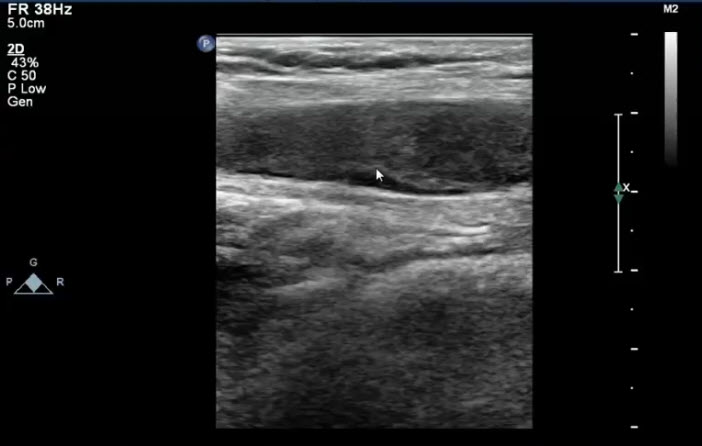

См клиник узи вен

См клиник узи вен 104 фотографий